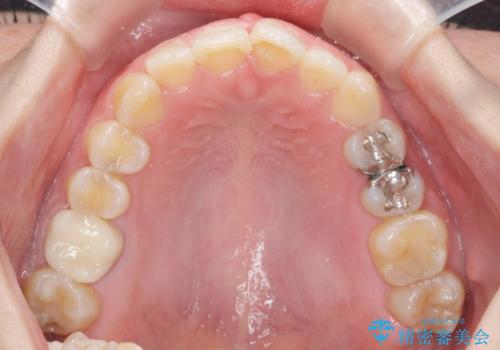

ねじれた前歯を改善するマウスピース矯正

- 大きくねじれた前歯をまっすぐに並べたい。と矯正治療を希望され来院されました。

前歯をきっちり並べるには奥歯の噛み合わせの調整を行い上下の前後的関係を治し、ねじれを取るスペースを確保していきます。

当初前歯だけ治れば良い、という心算で来院されましたが奥歯の噛み合わせも負担が大きく問題の起きやすいことをお伝えし上顎の奥歯をきっちりと後方移動行い噛み合わせの調整を行いました。・